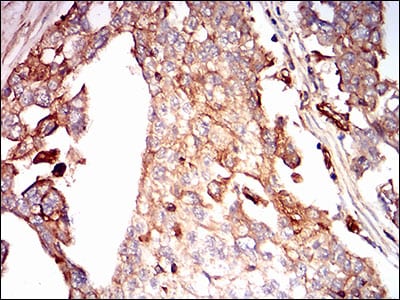

Immunohistochemical analysis of paraffin-embedded human ovarian cancer tissues using SDC1 mouse mAb with DAB staining.